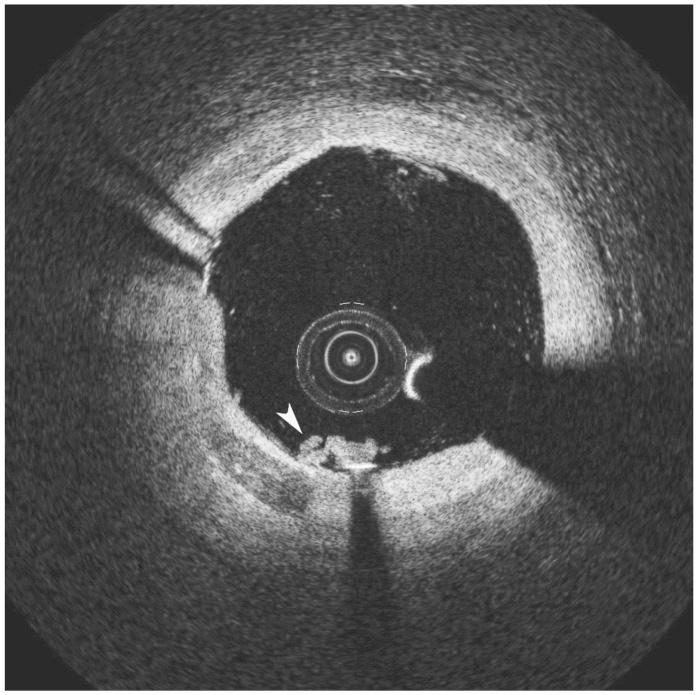

Although its use in daily practice is not common, optical coherence tomography (OCT) is a powerful research tool in invasive cardiology. This report describes a hazy angiography image after percutaneous coronary intervention that has been assessed using OCT. Based on the results of the OCT, the patient underwent an elective coronary angioplasty with standard anticoagulation. After implantation of the stent, an intracoronary hazy image was seen on angiography. The use of OCT permitted a correct diagnosis and a successful treatment. This paper provides a discussion of the advantages and disadvantages of OCT, and a comparison with intravascular ultrasound.

虽然在日常实践中并不常用,但光学相干断层扫描(OCT)是介入心脏病学中强有力的研究工具。本报告描述了经皮冠状动脉介入治疗后使用 OCT 评估的模糊血管造影图像。根据 OCT 的结果,患者接受了标准抗凝的选择性冠状动脉血管成形术。支架植入后,血管造影显示冠状动脉内出现模糊图像。OCT 的使用可以明确诊断并成功治疗。本文讨论了 OCT 的优缺点,并与血管内超声进行了比较。